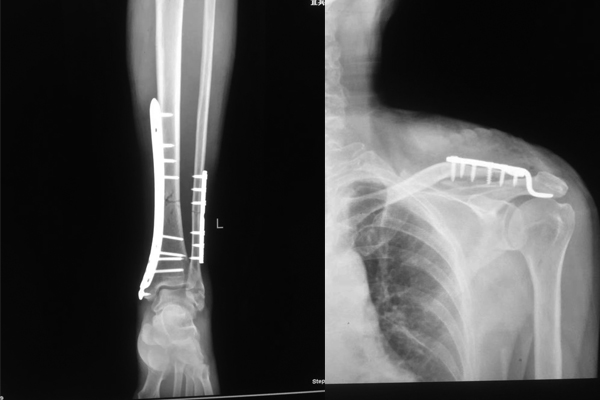

DR检查,被诊断为“左腓骨中下段粉碎性骨折、左内踝骨折、左外踝骨折、左锁骨远端粉碎性骨折”

手术后.jpg

入院不久后,在宜宾民心创伤骨科医院骨科主任的带领下,医疗团队先后为王某成功实施了“左腓骨、左内踝切开复位内固定术+左锁骨切开复位内固定术”

术后一个月,王某已经能丢拐下地行走,目前,王某的伤已经痊愈,近日就可以安然出院了。